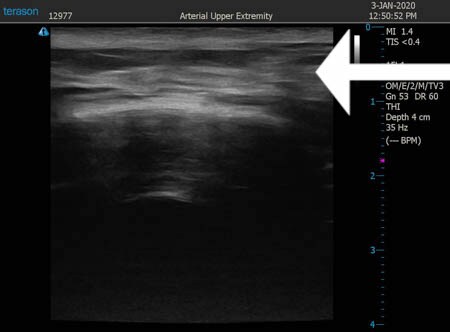

同様に右肩甲骨横 ↓ ↓ ↓

↓ ↓ ↓